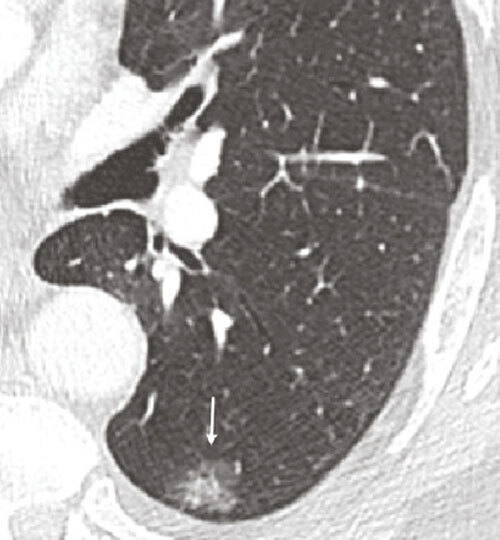

Le dépistage repose sur la réalisation d’un scanner thoracique à faible dose sans injection chez des personnes asymptomatiques ayant un risque élevé de ce cancer (fumeurs ou anciens fumeurs). En cas d'anomalie, le bilan diagnostique comporterait des examens complémentaires d'imagerie et une biopsie de la tumeur.